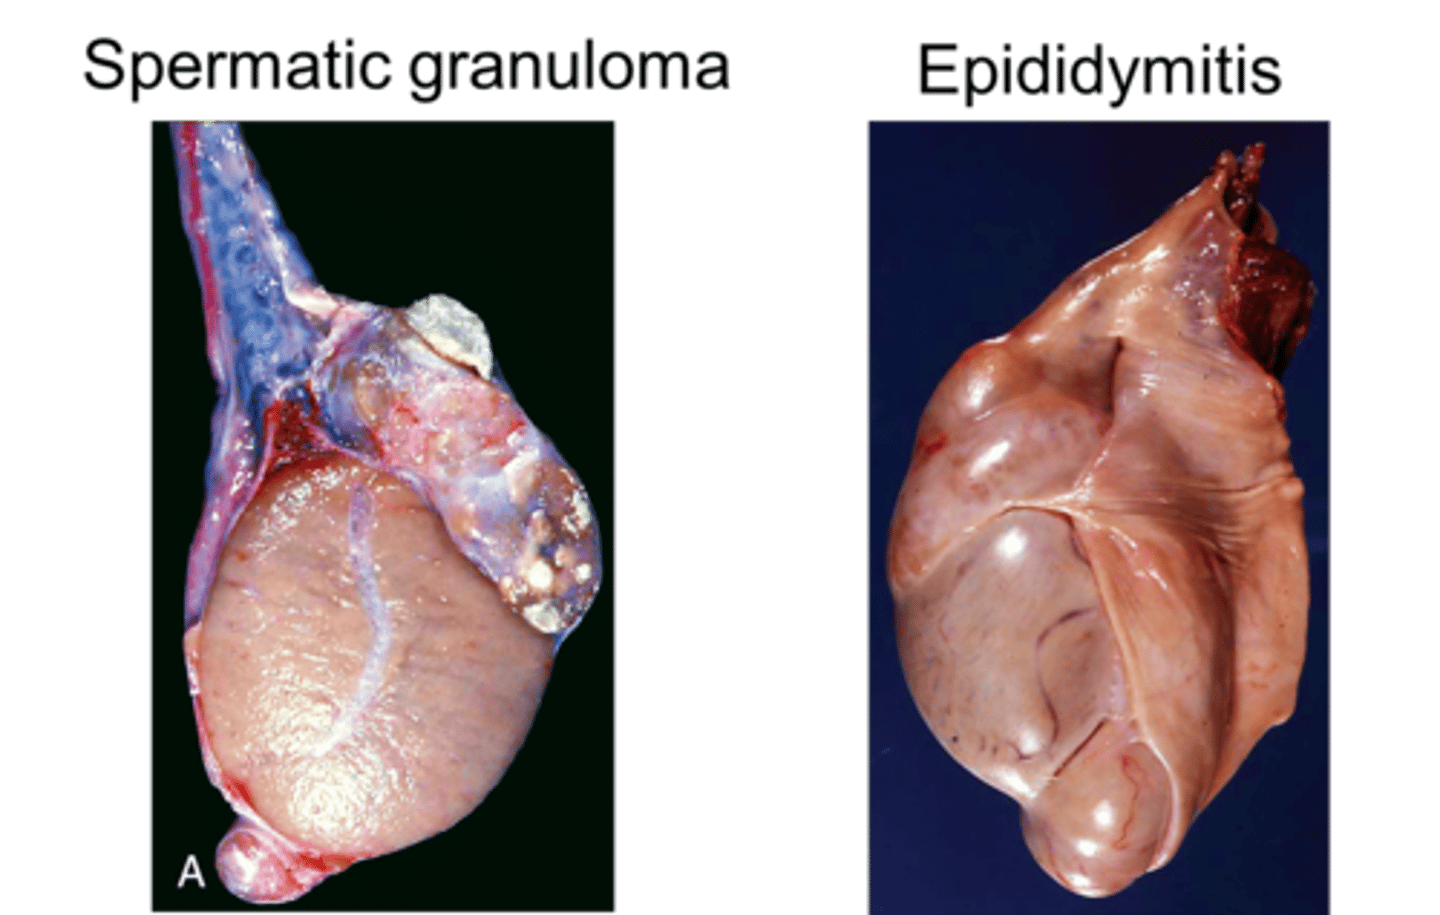

Epididymitis

Inflammation of the epididymis

- Almost always affects the tail of the epididymis (different from spermatic granuloma of the epididymal head)

What is spermatic granuloma?

- Spermatic granuloma is an inflammatory condition not caused by infection, but as response to extravasated spermatozoa (like from vasectomy/trauma/obstruction)

- The inflammation predominantly involves the efferent ducts (which are part of the spermatic duct system) and can spread to the head of the epididymis as well.

-get incrs in size of head of epididymis

in epididymitis what incrs in size

the whole of the epididymis